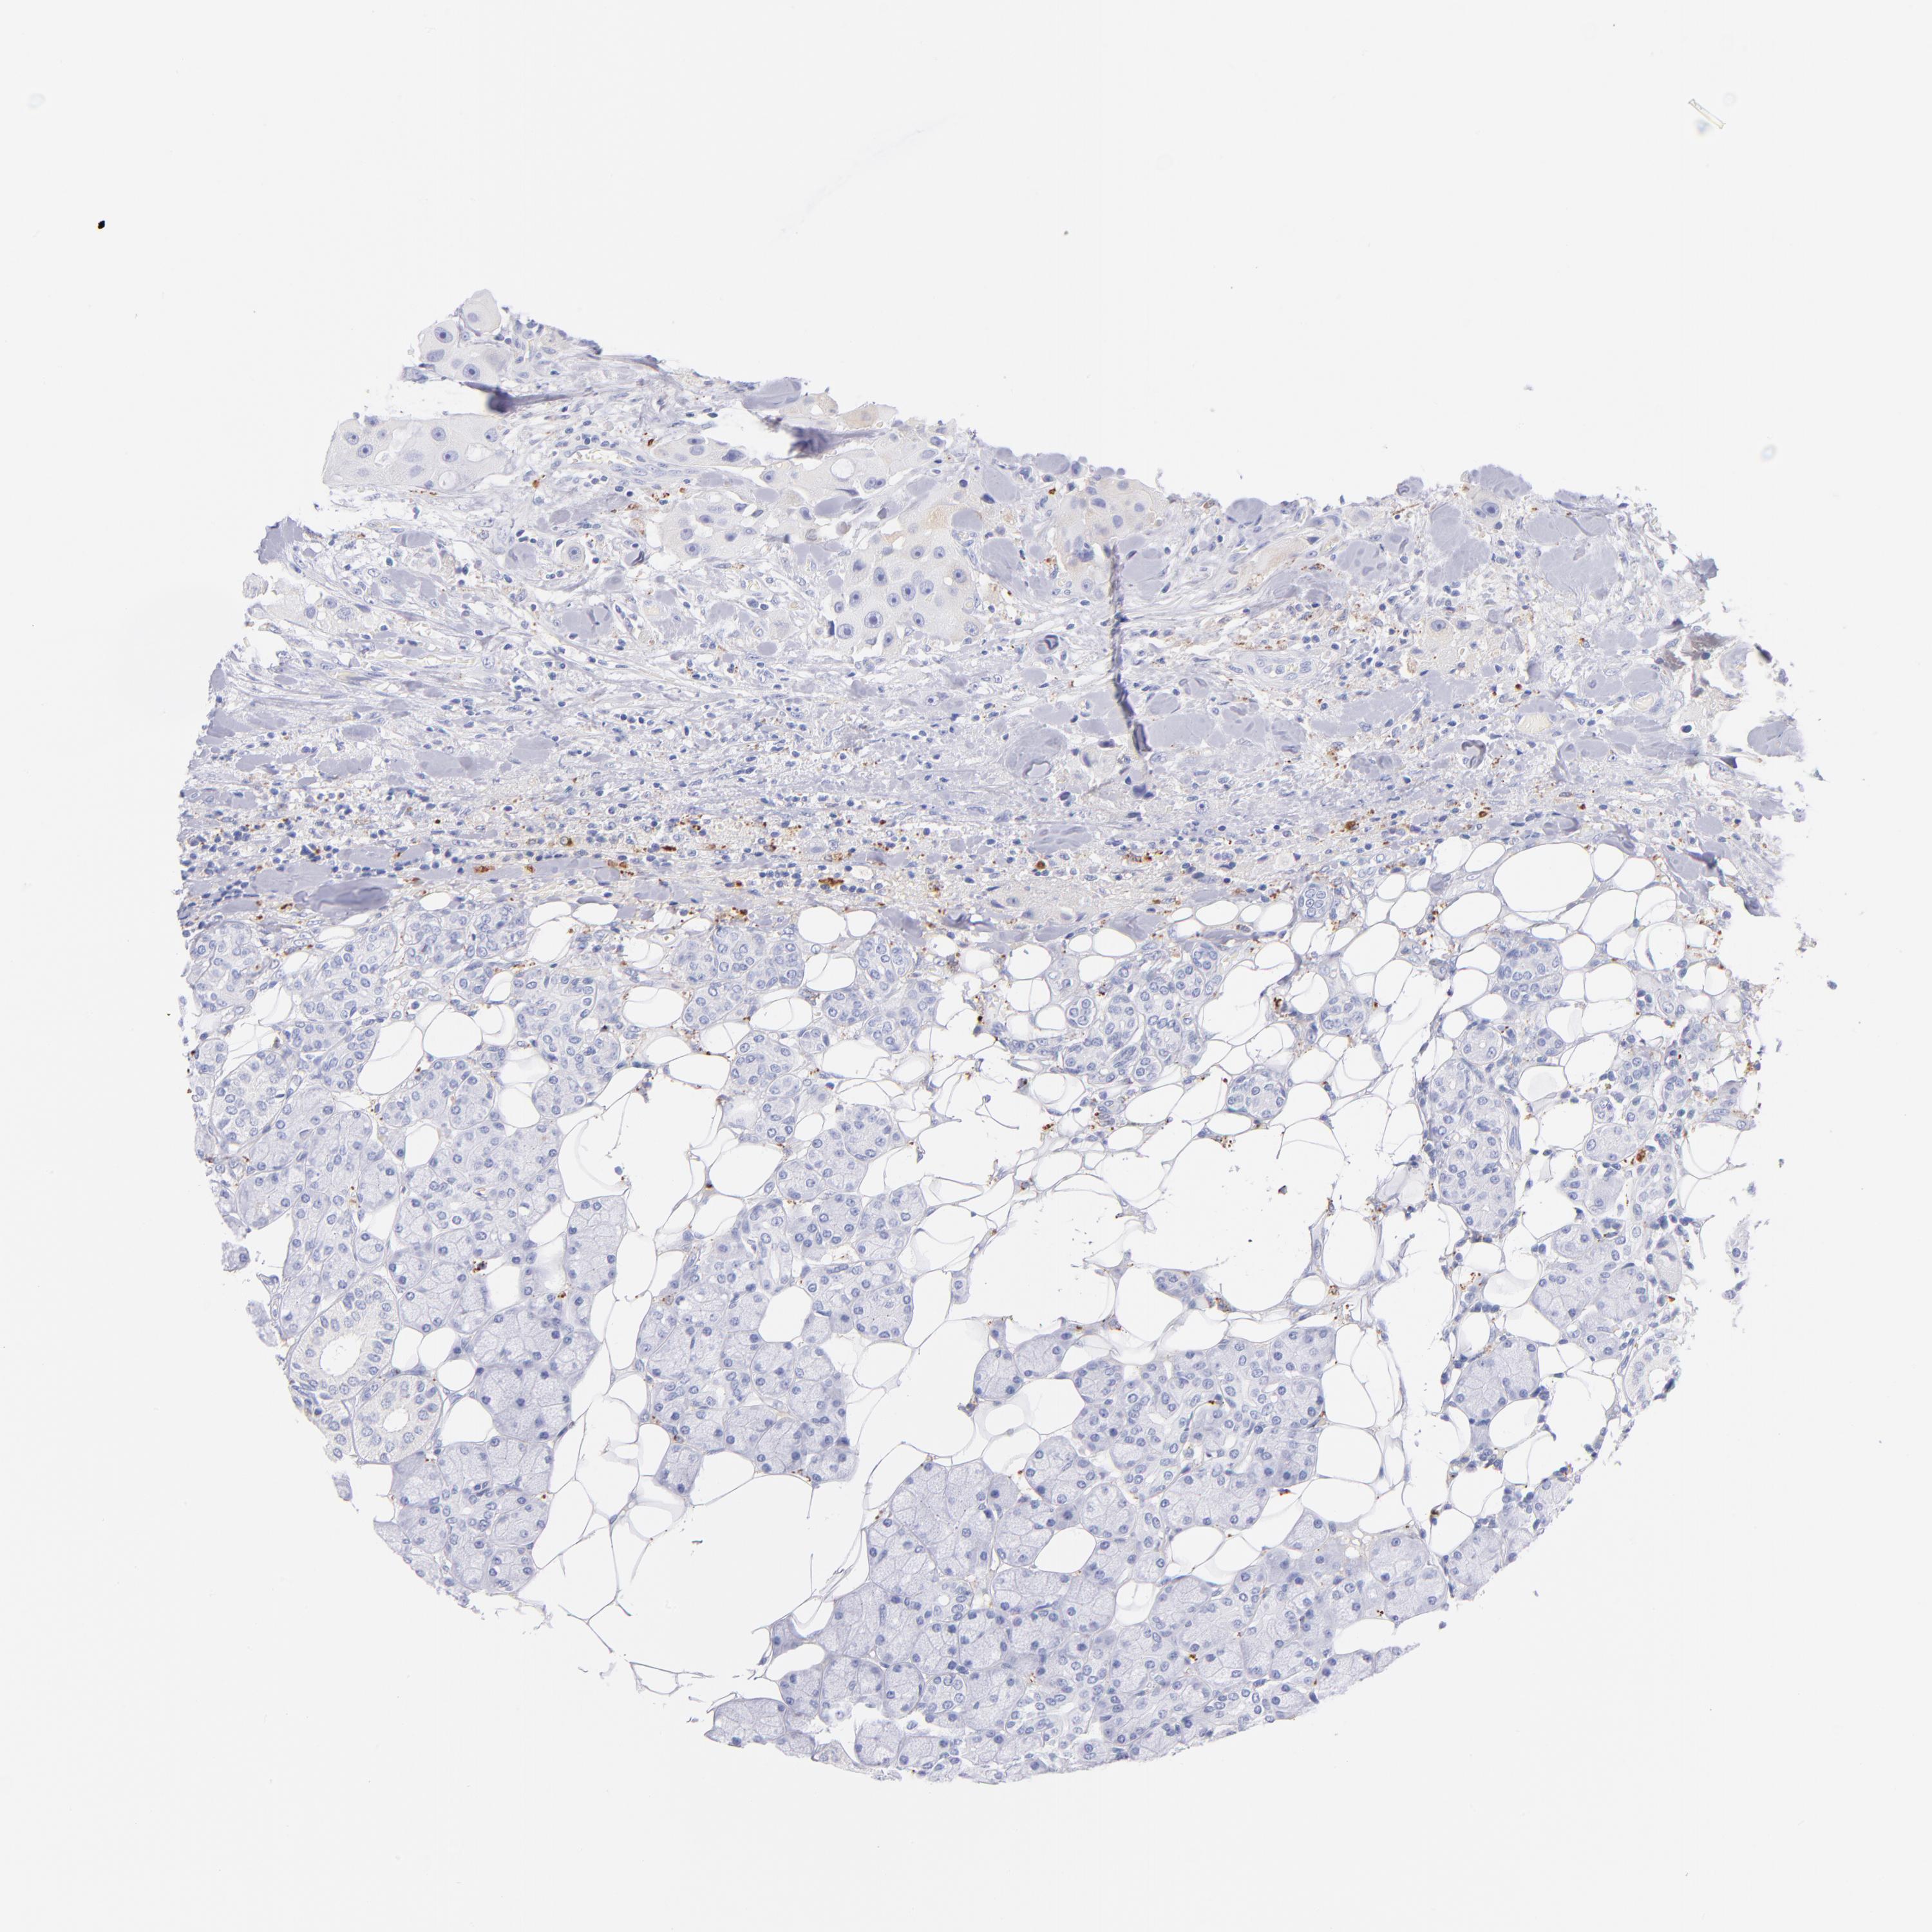

HEAD AND NECK CANCER - Protein expressioni

A mouse-over function shows sample information and annotation data. Click on an image to view it in a full screen mode. Samples can be filtered based on level of antibody staining by selecting one or several of the following categories: high, medium, low and not detected. The assay and annotation is described here.

Antibody stainingi

Antibody staining in the annotated cell types in the current human tissue is reported as not detected, low, medium, or high, based on conventional immunohistochemistry profiling in selected tissues. This score is based on the combination of the staining intensity and fraction of stained cells.

Each image is clickable and will lead to virtual microscopy that enables deeper exploration of all samples and also displays staining intensity scores, fraction scores and subcellular localization as well as patient and tissue information for each sample.

Antibody HPA047750

Antibody HPA066795

Antibody CAB003787

Staining

High

Medium

Low

Not detected

Intensity

Strong

Moderate

Weak

Negative

Quantity

>75%

75%-25%

<25%

None

Location

Nuclear

Cytoplasmic/membranous

Cytoplasmic/membranous,nuclear

Squamous cell carcinoma, NOS

Squamous cell carcinoma, metastatic, NOS

Adenocarcinoma, NOS

Adenocarcinoma, metastatic, NOS

Neoplasm, malignant, NOS